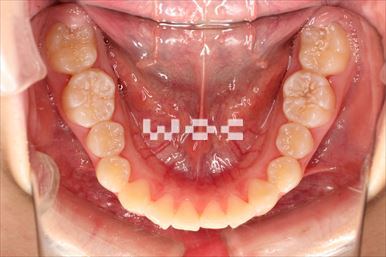

出っ歯舌側矯正

上下舌側矯正を希望。

通院状況や歯みがきの協力が良かったため、1年7ヶ月で治療を終えることができました。※装置と注意事項に関しては、大人の矯正装置一覧へ。

- 年齢:20歳女性

- 主訴:出っ歯が気になる

- 基本矯正料金:120万円

- 治療期間:1年7ヶ月

- 抜歯部位:上顎両側第一小臼歯